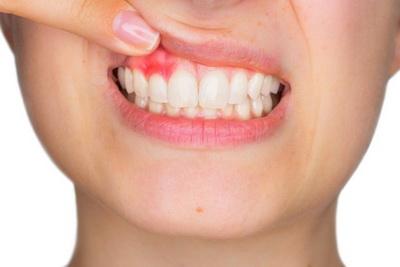

- Красная шишка (или цвета десны) чаще всего встречается при эпулисе, гематоме (тёмно-красная), челюстных опухолях или прорезывании зубов. Ярко-красная шишка с гнойным содержимым наблюдается при абсцессе или периостите.